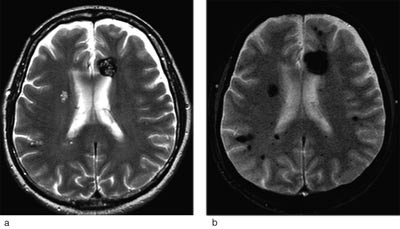

Malformasjonene har svært redusert perfusjon slik at de som regel ikke ses ved angiografiske undersøkelser. MR-skanning med gradientekko T2*-sekvens av hjerne og medulla er den bildediagnostiske metode med best sensitivitet (4, 6). Likevel får 2 - 3 % med den familiære formen ikke påvist noen forandringer ved MR- undersøkelse. 13 % av dem med familiær form har en enkelt cerebral kavernøs malformasjon (6). Figur 2 viser MR-skanning av hjernen hos person med cerebrale kavernøse malformasjoner.